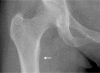

Vitamin D deficiency remains common and may mimic other musculoskeletal disorders or mental health problems